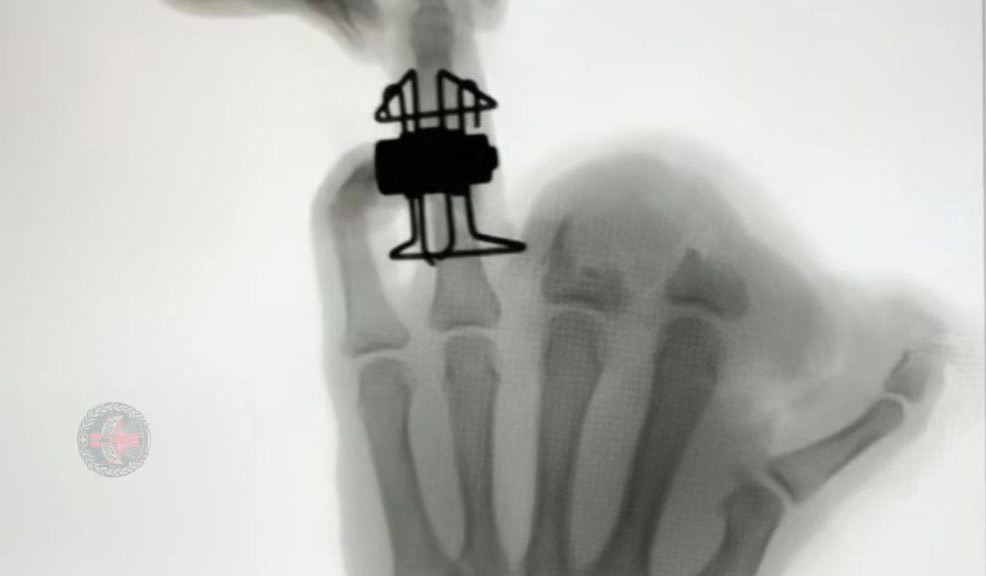

Военнослужащие тульского 39-го гвардейского ОМЕДО ВДВ России в своём телеграм-канале рассказали об инновации в лечении сложных переломов пальцев. В практике лечения оскольчатых и сложных переломов фаланг пальцев, включая огнестрельные, аппарат Suzuki (так называемая «рама Suzuki») долгое время оставался одним из основных инструментов.

Среди его преимуществ – дистракционный принцип действия и возможность постоянного растяжения отломков. Но есть и недостатки: из-за нерегулируемой тракция существует высокий риск перерастяжения, а сам аппарат нельзя использовать слишком долго.

Наши военные врачи, спасающие бойцов в зоне СВО, разработали новый мини-аппарат внешней фиксации, который сохраняет преимущества аппарата Suzuki, но лишён его ключевых недостатков. Точная дозировка тракции позволяет регулировать силу растяжения.  Кроме того, скорректировать настройку аппарата можно в любой момент, адаптировав его работу под динамику сращения костей.

Разработка велась совместно с кафедрой травматологии и ортопедии Тверского ГМУ. Первая в России операция с применением нового аппарата уже состоялась и была завершена успешно.  Сейчас изобретение проходит патентование, но уже активно используется в практике 39-го гвардейского ОМЕДО, помогая восстанавливать поврежденные пальцы бойцов.